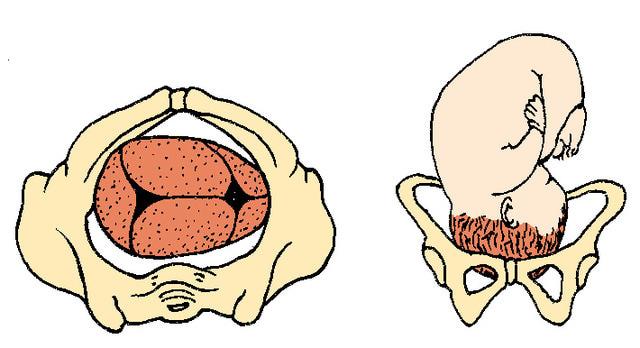

Complete Breech

Frank Breech

Footling Breech

What are the two footling breech positions?

single footling

double footling

How many babies are breech at term?

3% to 4%